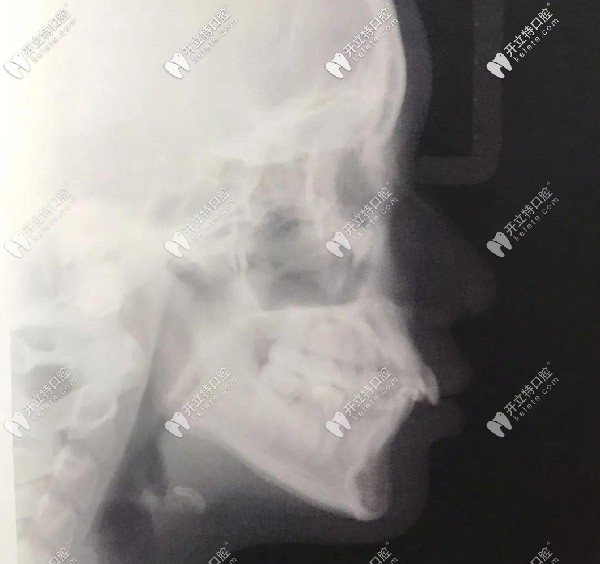

側(cè)面X光,門牙唇傾很厲害的

▲側(cè)面X光,門牙唇傾很厲害的